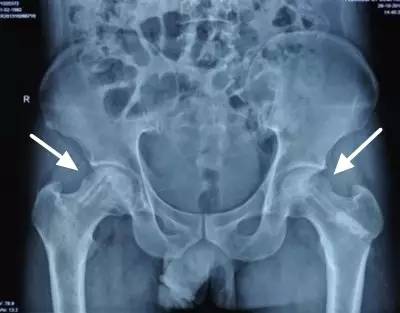

股骨头坏死

股骨头坏死又称股骨头无菌性坏死,或股骨头缺血性坏死,是骨坏死的一种。股骨头局部血运不良,引发股骨头血液循环障碍,从而使得股骨头进一步缺血、坏死、骨小梁断裂、股骨头塌陷的一种病变。因其病因多样、发病隐匿、治疗周期长、致残率高的特点,又被称为“不死的癌症”。

股骨头坏死的诊断

股骨头坏死的治疗效果与病情轻重、发现早晚、病程分期有很大关系,病变发现越早,病情越轻,治疗效果就越好,因此股骨头坏死应做到早期诊断和早期治疗。髋 关节核磁共振、髋关节CT以及同位素骨显像等影像学检查虽然价格较X线片贵,但是往往可以帮助医师更早地发现股骨头坏死。